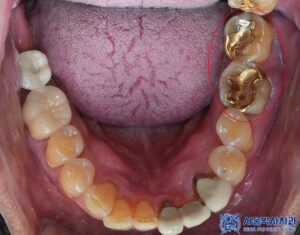

이번에 내원하신 환자분은

왼쪽 어금니 아래쪽이 많이 부으셔서

음식을 잘 못 씹는 상태로

집 근처 치과를 찾아보시다

산성동치과 서울박사에

내원해 주셨습니다.

확인해 보니,

왼쪽 아래 어금니의

치주염으로 인해

통증이 심한 것으로

확인할 수 있었습니다.

또한 앞니의 충치도 있었으며,

왼쪽 위 작은 어금니

기존 충전재 하방의 충치가

관찰되었습니다.